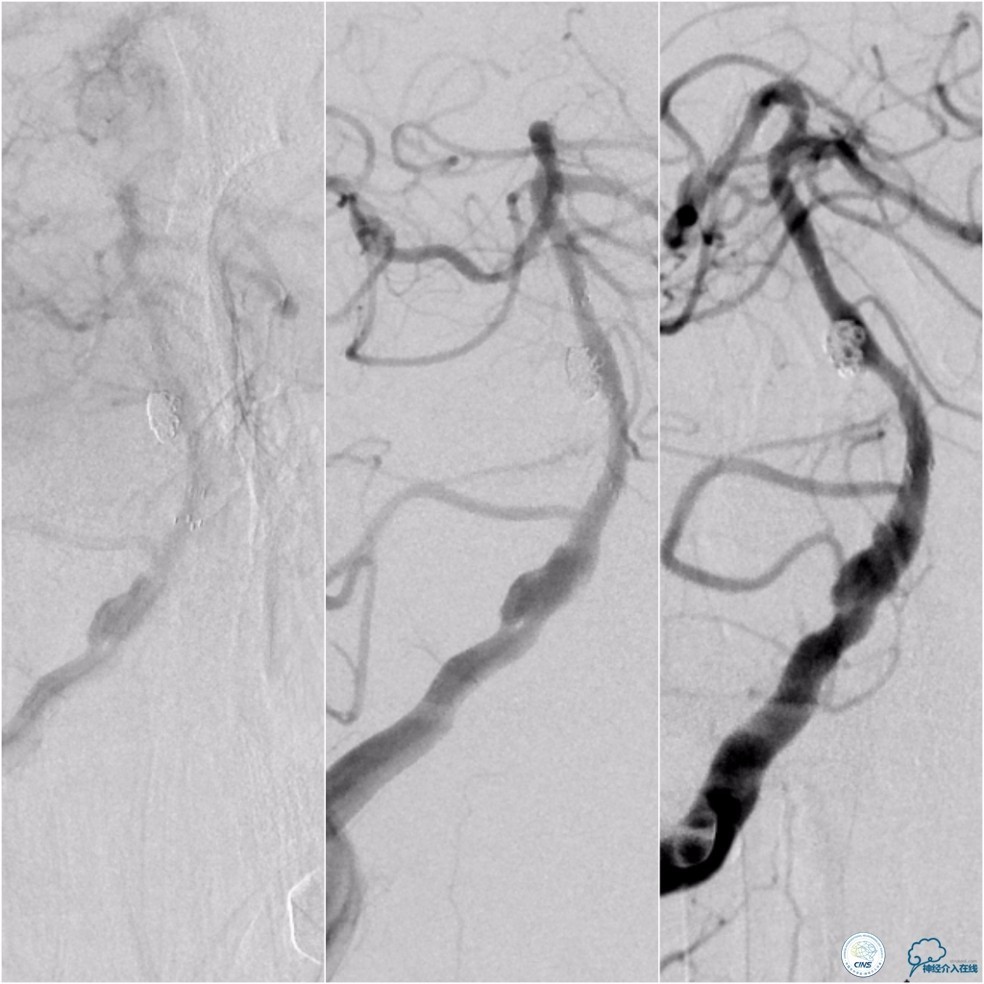

术前DSA:基底动脉中段狭窄,狭窄远端动脉瘤,右椎动脉优势,右椎V4段管壁不光滑(图7)。

图7

左椎动脉V3段以远未见显影(图8)。

图8

前循环未见明显向后循环代偿(图9)。

图9